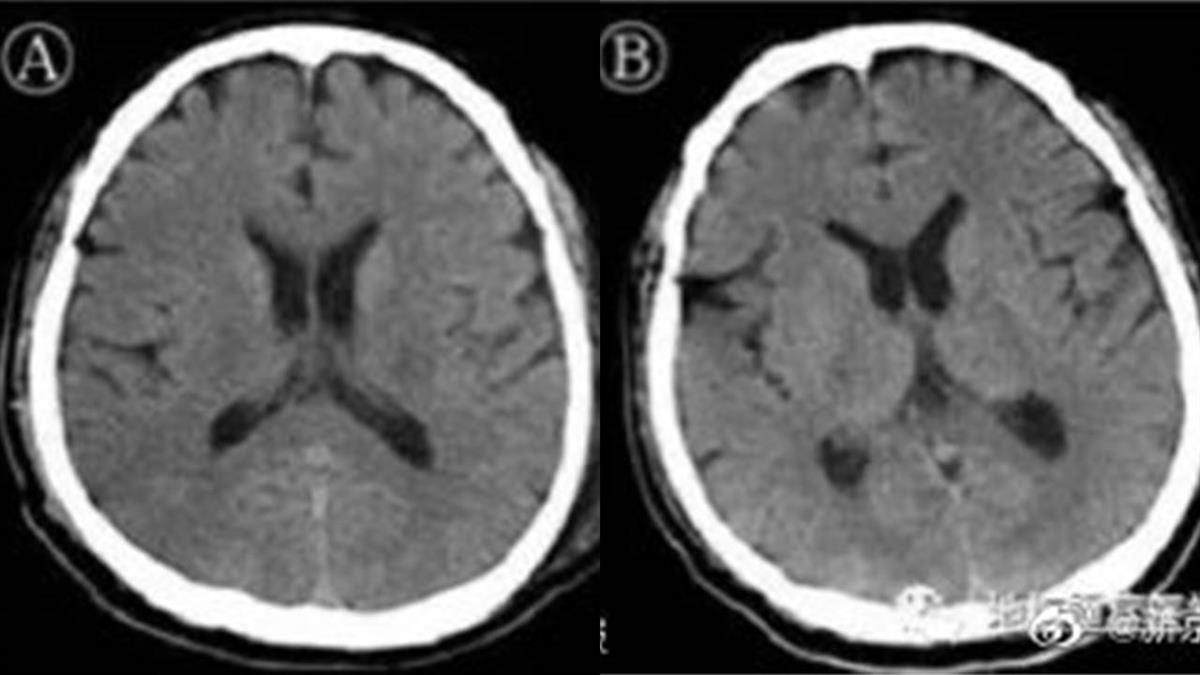

大陸北京醫院證實,武肺病毒會攻擊中樞神經!北京地壇醫院治癒了一名危重症患者,一開始有呼吸衰竭等症狀,治療卻沒效果,狀況還越來越差,後來發現他出現「意識障礙」,臨床診斷出他是病毒性腦炎,最後在團隊的努力下治癒出院,這也是全球首例武漢肺炎併發腦炎!

▼北京地壇醫院治癒了一名遭武肺病毒攻擊中樞神經的患者。(圖/翻攝自首都醫科大學附屬北京地壇醫院官網)

北京地壇醫院醫師證實,新冠肺炎不只會攻擊心臟,肺部,臟器等器官,甚至出現了全球首例病毒攻擊中樞神經,因此併發腦炎。會發現就是因為醫師對他做各種的治療都沒效,患者出現意識障礙。

大陸新聞片段:「患者如果出現意識障礙,一定要考慮病毒有可能攻擊中樞神經系統。」